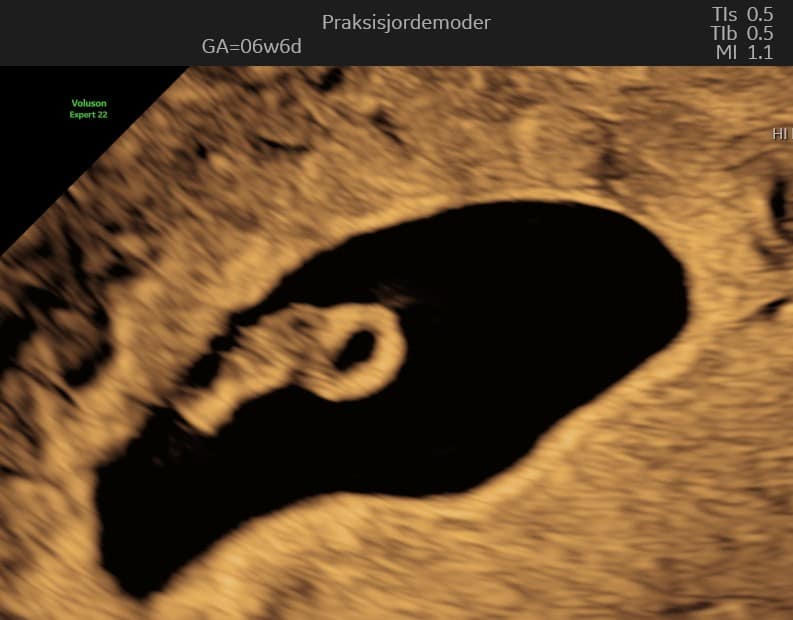

Uge 7: Embryoets Udvikling

I slutningen af uge 7 er din lille baby omkring 1,1 cm langt, omtrent på størrelse med et blåbær. Der sker mange vigtige udviklinger denne uge:

Hjerne og Nervesystem: Hjernen vokser hurtigt, og der dannes primære hjerneanlæg. Nervesystemet er i fuld gang med at udvikle sig og begynder at sende de første nerveimpulser.

Ansigtstræk: Embryoets ansigt begynder at tage form. Små næsebor dannes, og linsen i øjet begynder at udvikle sig. Ørerne begynder at forme sig som små folder på hver side af hovedet.

Lemmer: Arm- og benknopper bliver længere, og små finger- og tåanlæg begynder at danne sig. De ligner små padleformede udvækster på dette stadie.

Organudvikling: Hjertet er nu opdelt i højre og venstre kammer og slår i en jævn rytme. Lunger, tarm og nyrer fortsætter med at udvikle sig. Leveren begynder at danne røde blodlegemer.